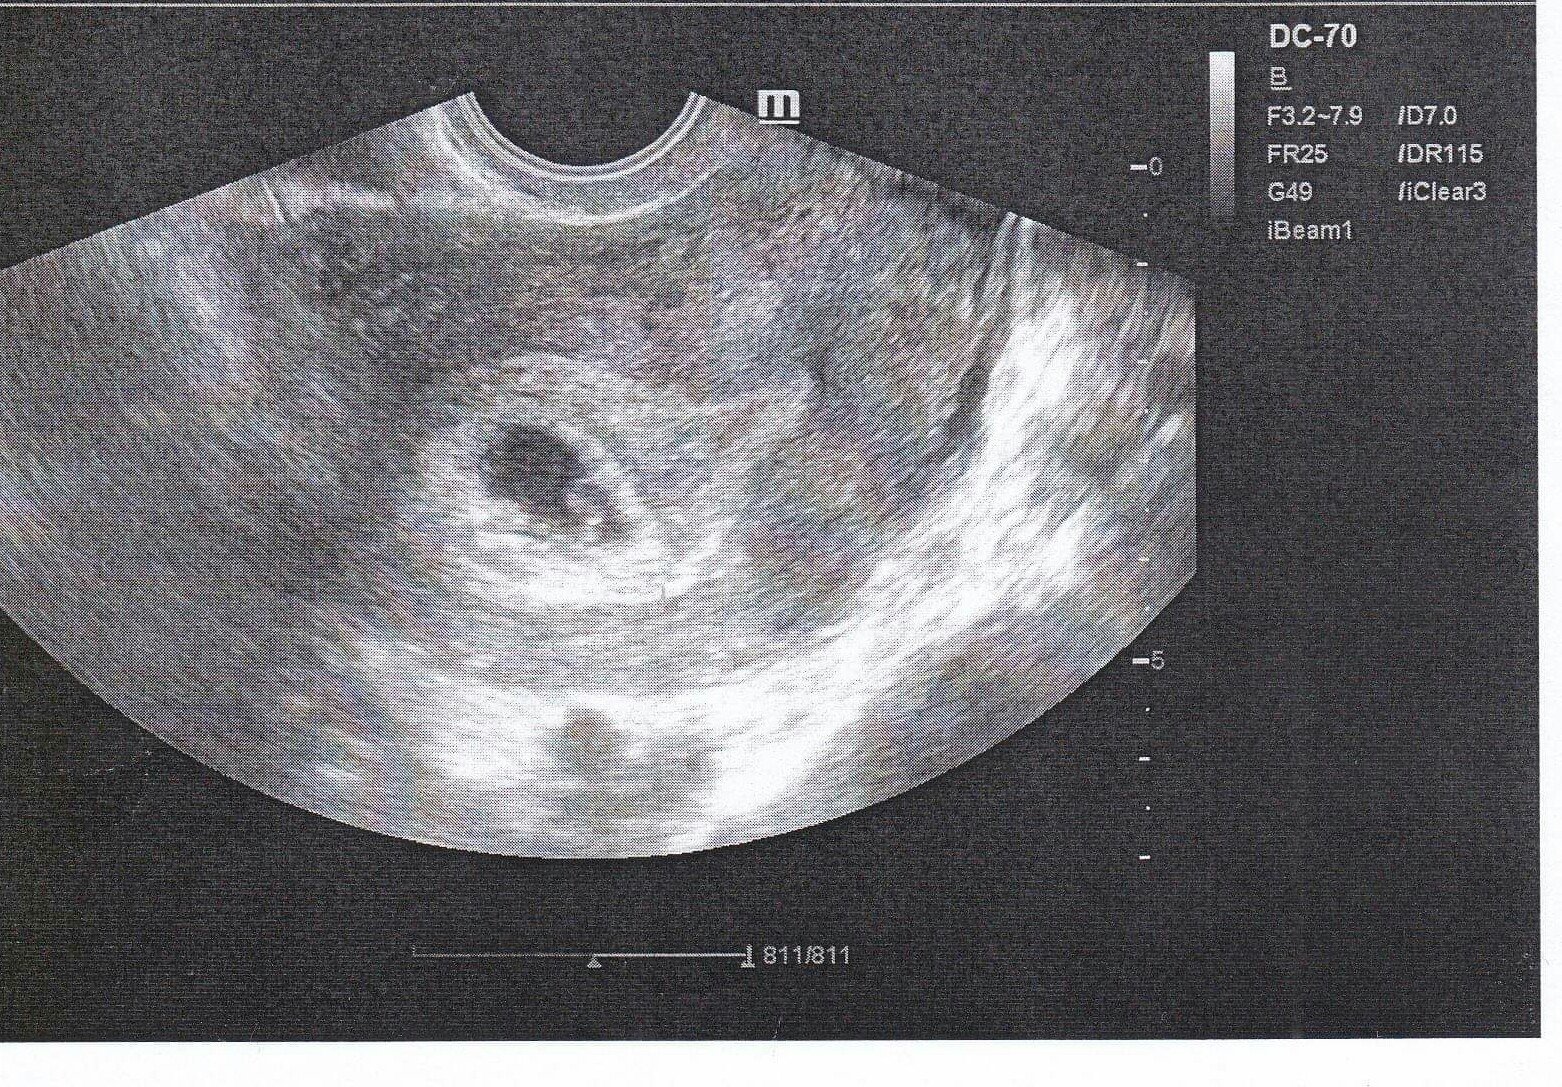

Este ze idem zajtra na sono.... Uvidime, co tam najdu :D graf bol ok kym som nezaznacila dnesne tutu mutu a ovulak...